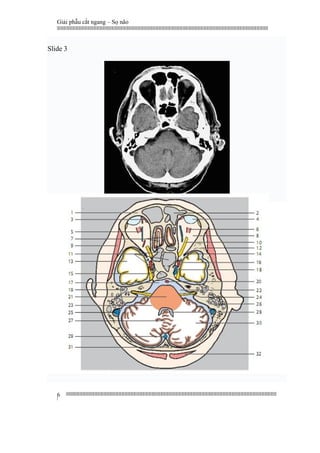

Slide 3

1 Frontal bone

2 Frontal sinus

3 Superior oblique muscle

4 Eyeball

5 Ophthalmic vein

6 Superior rectus muscle

7 Straight gyrus and olfactory bulb

8 Retro-orbital fatty tissue

9 Temporal muscle

10 Optic nerve

11 Sphenoidal sinus

12 Sphenoidal bone

13 Inferior temporal gyrus

14 Superior orbital fissure

15 Trigeminal nerve (ganglion)

16 Internal carotid artery

17 Pontinecistern

18 Cavernous sinus

19 Mastoid antrum

20 Basilar artery

21 Pons

22 Ponto cerebellar cistern

23 Middle and inferior cerebellar

peduncle

24 Internal auditory meatus with facial

(VII) and vestibulocochlear /acoustic

(VIII) nerves

25. Sigmoid sinus

26. Mastoid process with mastoid cells

27. Vermis of cerebellum

28. Fourth ventricle

29. Occipital sinus

30. Cerebellar hemisphere

31. Occipital bone

32. Semispinalis capitis muscle

1. Xương trán

2. Xoang trán

3. Cơ chéo trên

4. Nhãn cầu

5. Tĩnh mạch mắt

6. Cơ thẳng trên

7. Hồi thẳng và hành khứu

8. Mô mỡ sau nhãn cầu

9. Cơ thái dương

10. Thần kinh thị

11. Xoang bướm

12. Xương bướm

13. Hồi thái dương dưới

14. Khe ổ mắt trên

15. Hạch thần kinh sinh ba

16. Động mạch cảnh trong

17. Bể cầu não

18. Xoang hang

19. Hang chũm

20. Động mạch thân nền

21. Cầu não

22. Bể góc cầu - tiểu não

23. Cuống tiểu não giữa và dưới

24. Ống tai trong với các cấu trúc thần kinh

mặt VII và tiền đình ốc tai

25. Xoang sigma

26. Mỏm chũm với các khí bào chũm

27. Thùy nhộng tiểu não

28. Não thất tư

29. Xoang chẩm

30. Bán cầu tiểu não

31. Xương chẩm

32. Cơ bán gai